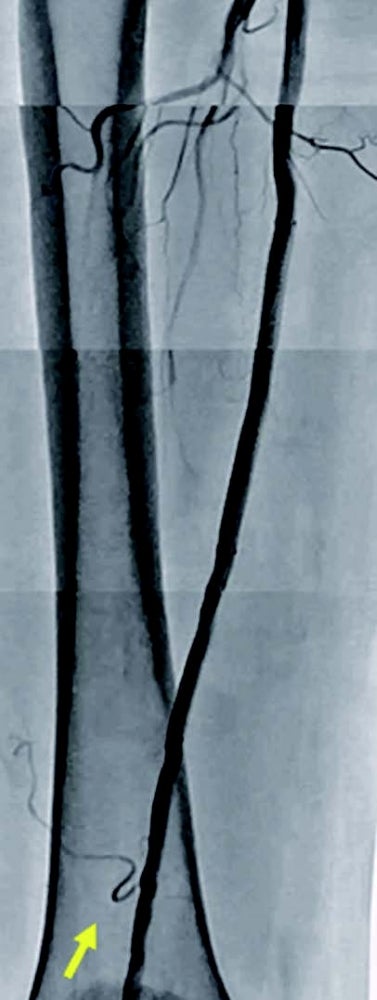

バイアバーン® ステントグラフト留置後3年経過した現時点において跛行症状の再発やTLR なく、ABI 値は正常値 ( 右1.05 左1.05) を維持し、良好。

両側浅大腿動脈閉塞病変に対してバイアバーン® ステントグラフトにて血行再建術を施行し、その後3年の経過において良好な経過をみている(図5)。側副血行路を温存するかどうかの議論はあるが、バイアバーン®ステントグラフトを健常部に留置し、遠位部に残存狭窄を残さないことが重要と考えている。さらに定期的な duplexでのフォローアップで、ステントedgeや中枢側の新規病変を早期発見し治療することが、ステント閉塞予防に不可欠と思い、実践している。最後に、長区域の浅大腿動脈病変の治療は、外科治療のオプションも見据え、血管外科医との連携は極めて重要と考えている。